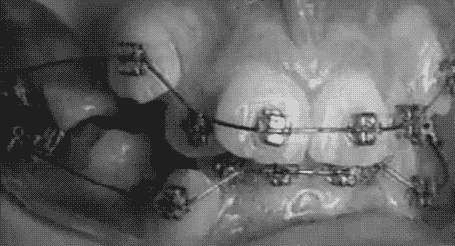

The most common orthodontic treatment is braces, which are made of bands, wires and brackets. They gently move teeth into the right position. This can fix the way you bite together. There are different types of braces. The most common are metal or plastic brackets attached to the front surface of the teeth. "Lingual" braces attach to the back of teeth. They are hidden from view but harder to clean.

plusdent brackets